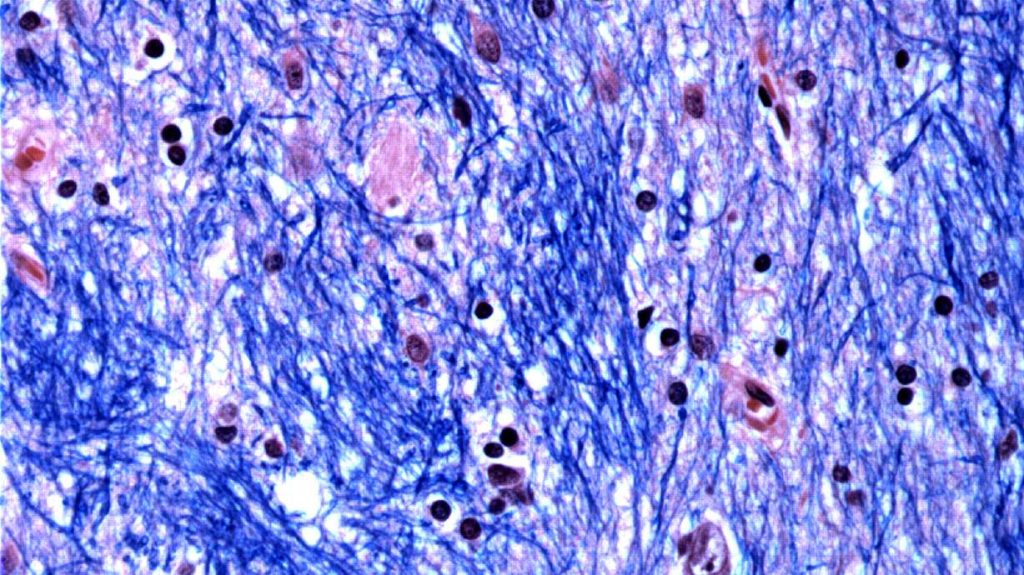

Finding sheds light on what causes Huntington’s disease, a devastating fatal brain disorder

BOSTON — Scientists are unraveling the mystery of what triggers Huntington’s disease, a devastating and fatal hereditary disorder that strikes in the prime of life, causing nerve cells in parts of the brain to break down and die. The genetic mutation linked to Huntington’s has long been known, but scientists haven’t understood how people could […]